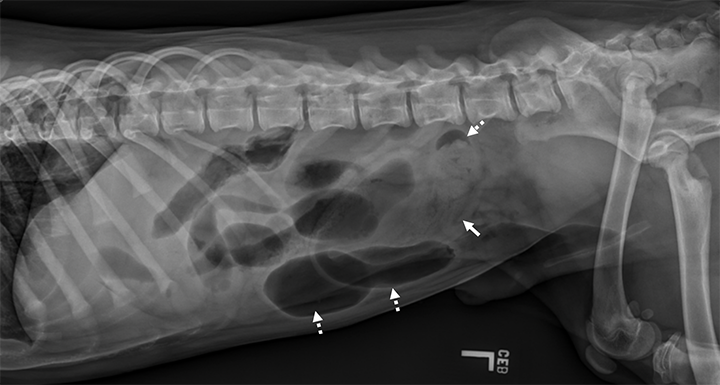

Radiology Case of the Week Canine Pleural Effusion

chest xray of a dog with heart disease pulmonic stenosis Stock

A Visual Guide to GI Obstruction on Radiographs